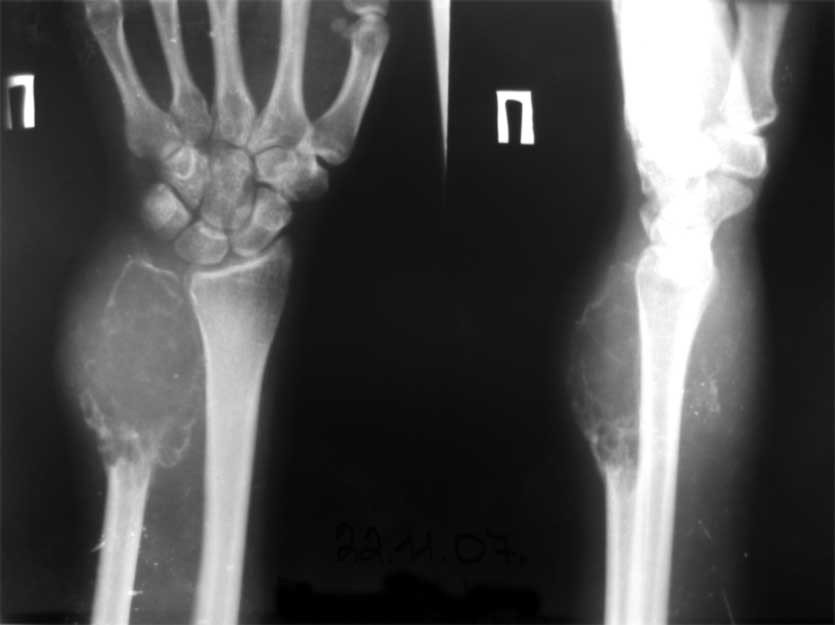

остеобластеокластома локтевой кости |

Обратилась пациентка 21 года с опухолью в области н/3 диафиза локтевой кости.

Первые жалобы появились около года назад. Снимков старых под рукой сейчас нет, но опухоль быстро прогрессировала, за полгода увеличилась в размерах более чем в 2 раза. Выполнено несколько гистологических исследований - стеобластеокластома без признаков озлокачествления. После заключительной биопсии на локтевой поврехности предплечья есть рана 5/7 см,не заживет на протяжении 2 мес (натяжение кожи над опухолью), гранулирует, небольшое количество налетов. Планируется резекция, продленная фиксация в гипсе/аппарате - 3-4 мес для формирования контрактуры, уменьшения риска локтевой девиации кисти.